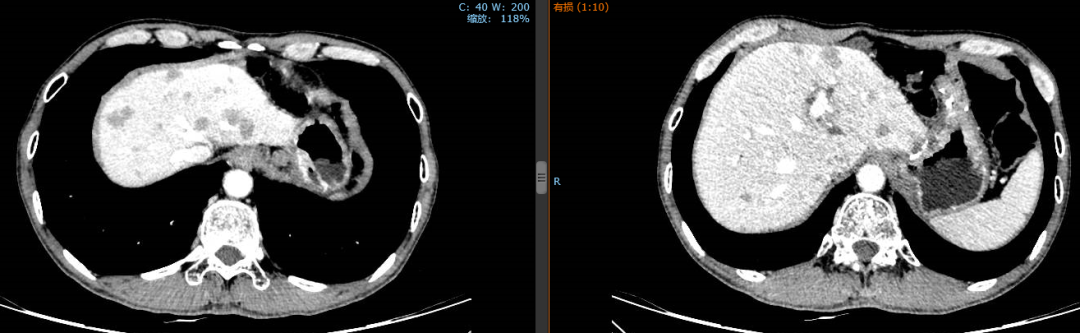

2019年1月24日,经4个周期赫赛汀+DF后,患者肝脏转移灶明显缩小。

2018年10月17日,化疗前

2019年1月24日,化疗后